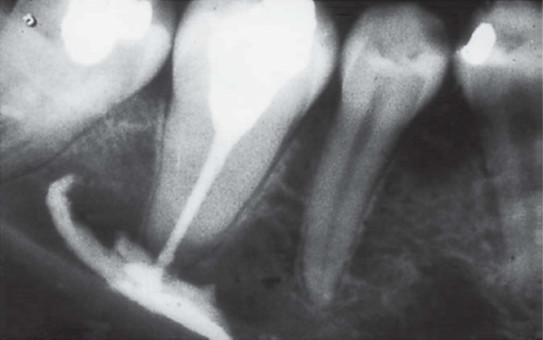

Jaka mogła być przyczyna resorpcji zęba widocznego na poniższym zdjęciu rentgenowskim?